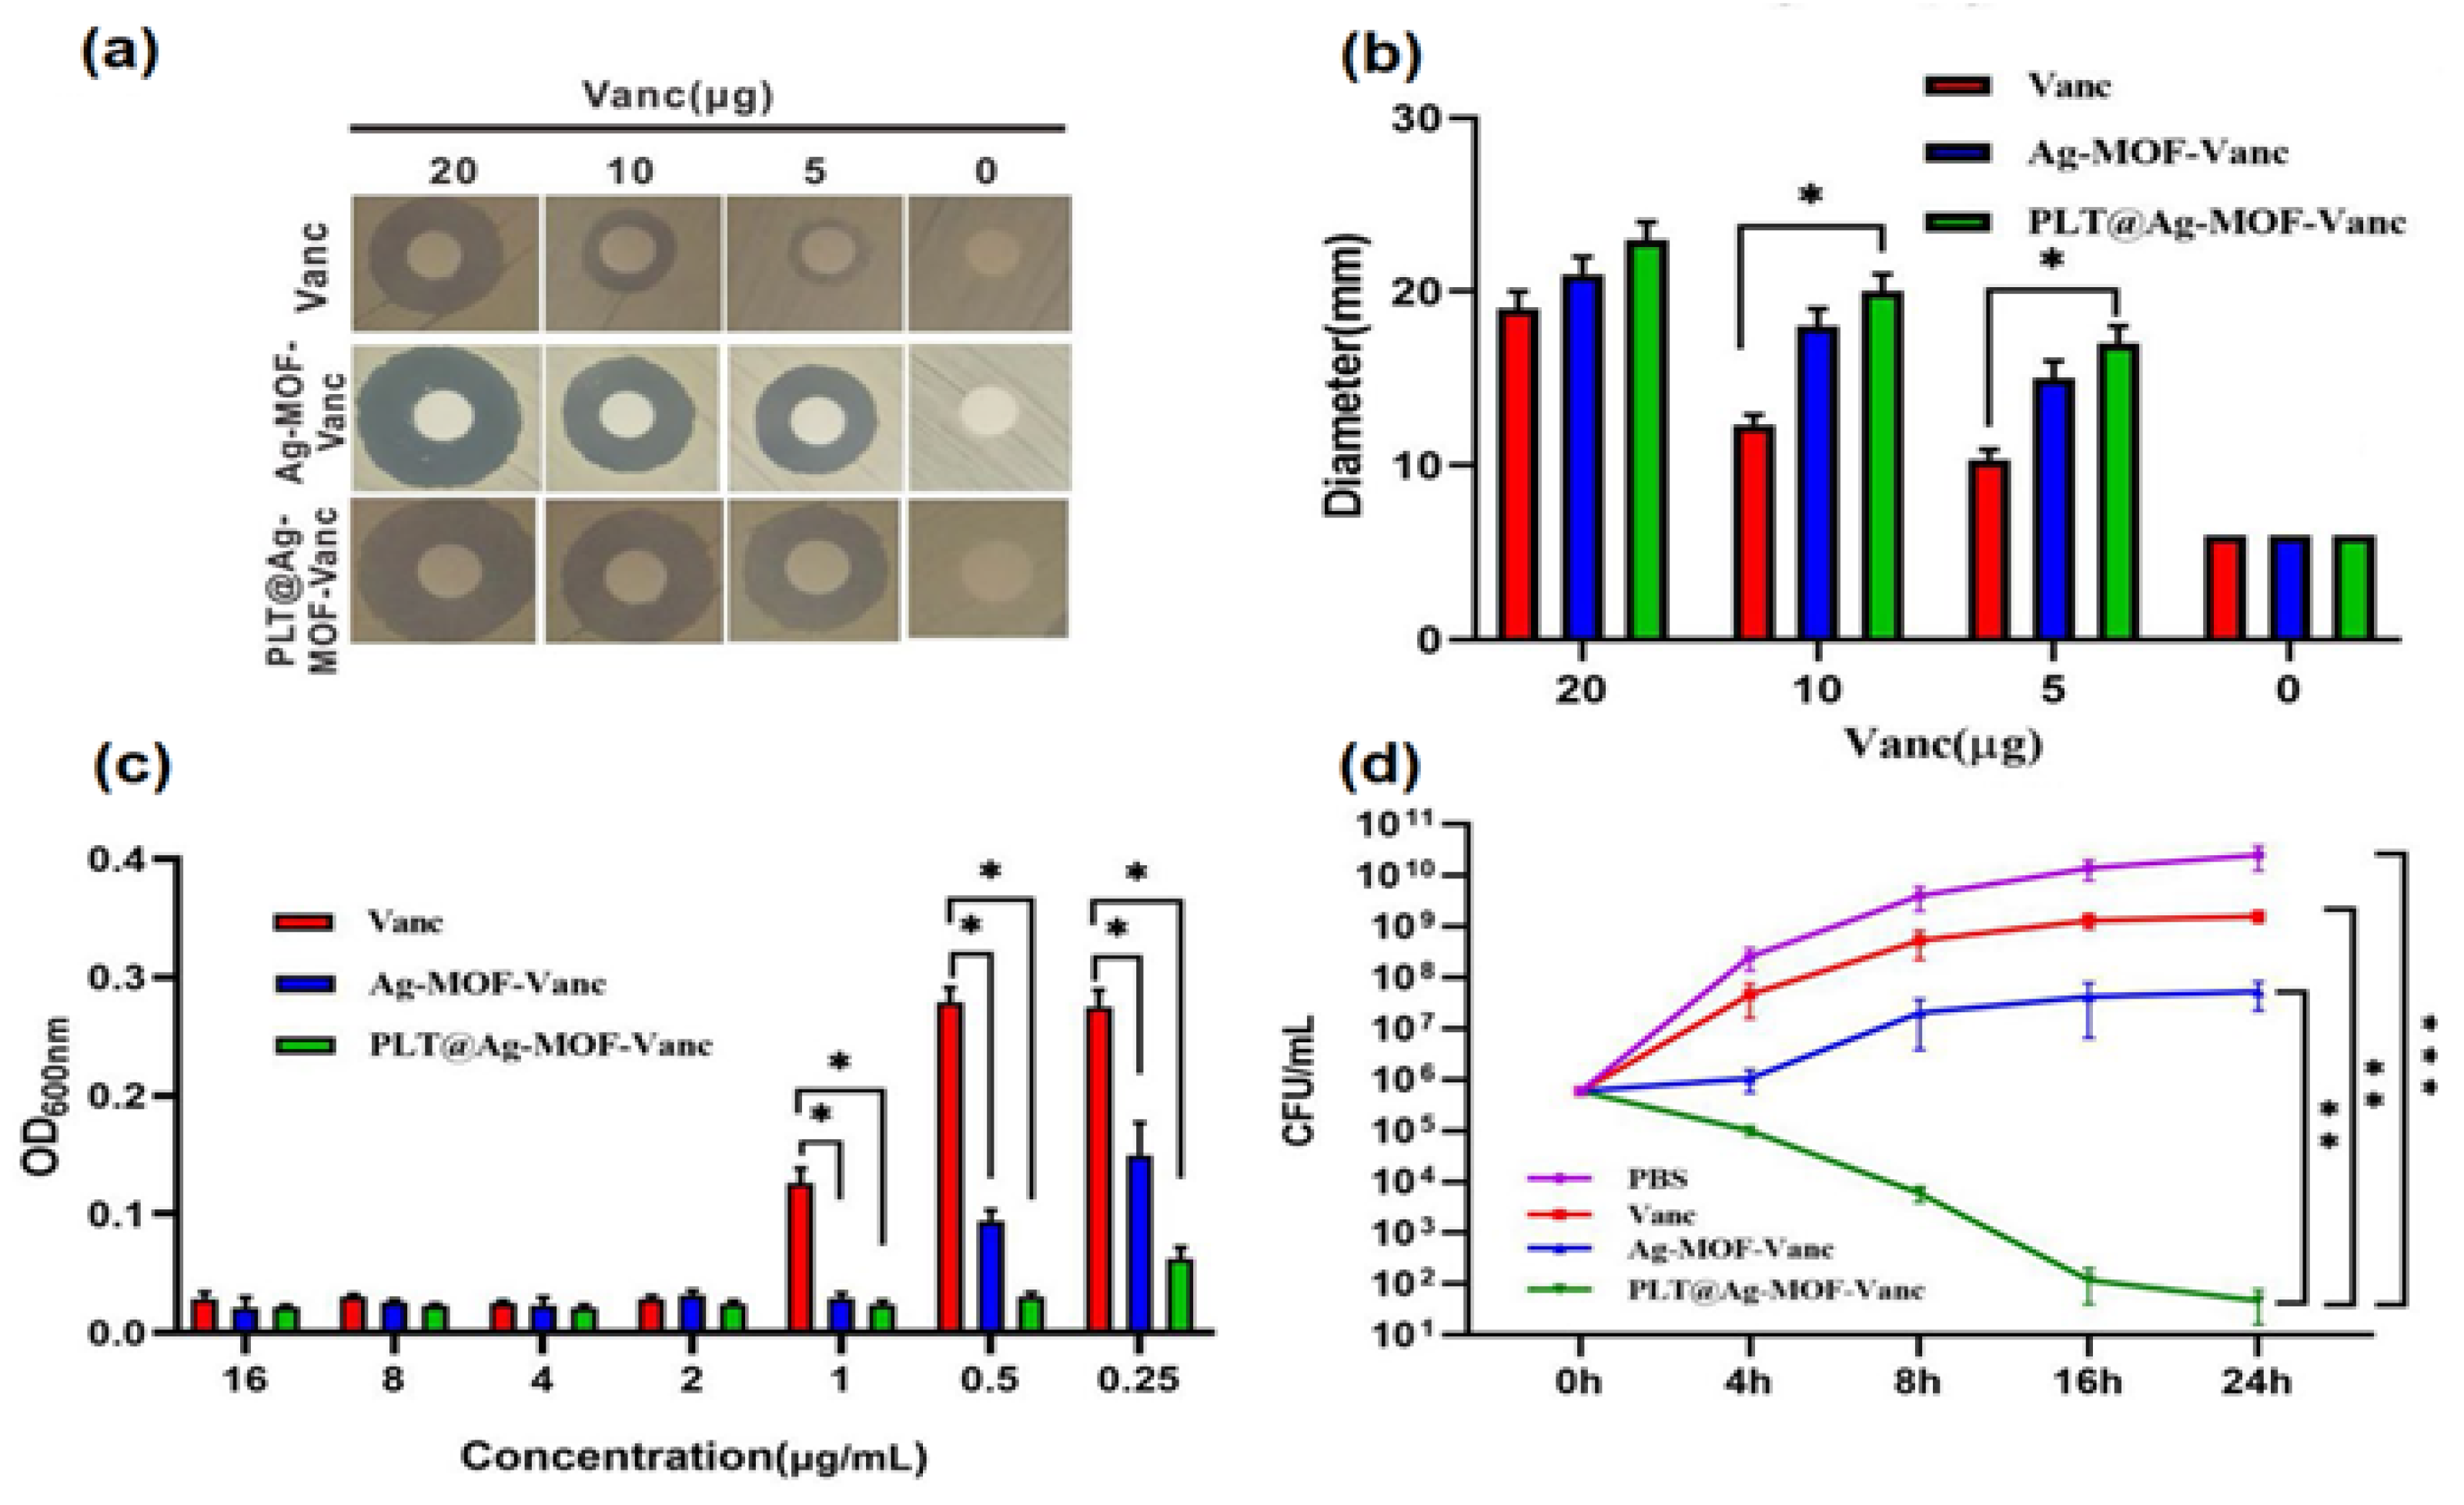

- Huang, R.; Cai, G.-Q.; Li, J.; Li, X.-S.; Liu, H.-T.; Shang, X.-L.; Zhou, J.-D.; Nie, X.-M.; Gui, R. Platelet Membrane-Camouflaged Silver Metal-Organic Framework Drug System against Infections Caused by Methicillin-Resistant Staphylococcus aureus. J. Nanobiotechnology 2021, 19, 229. [Google Scholar] [CrossRef] [PubMed]